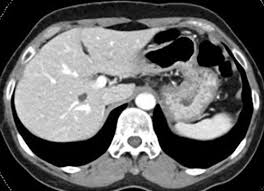

Abdomen CT-복부 전산단순촬영은 복부 소화기 질환, 외상성 출혈, 복수, 종양의 유무 등을 진단한다. 또한 비침투적이면서도 췌장 종양, 염증, 물혹, 복수, 간경화증의 정확한 진단을 할 수 있는 유용한 검사이다.

Abdomen CT-복부 전산단순촬영 영상 조영 CT 검사 전과 후 주의 사항